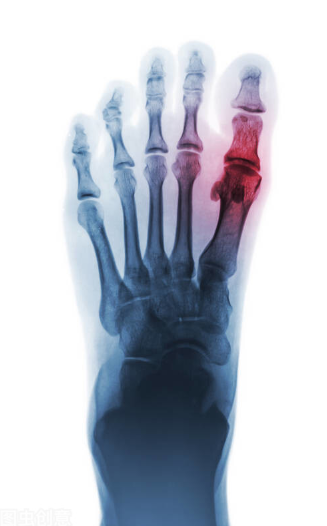

贵阳治疗痛风专科医院 针刀镜是种什么治疗方式?针刀镜治疗痛风

痛风的基础治疗以内科治疗为主,治疗一般按临床分期进行,包括急性发作期的药物治疗、中医理疗,缓解期和慢性痛风性关节炎期的降尿酸治疗,以及预防痛风急性发作的治疗三部…[查看详情]